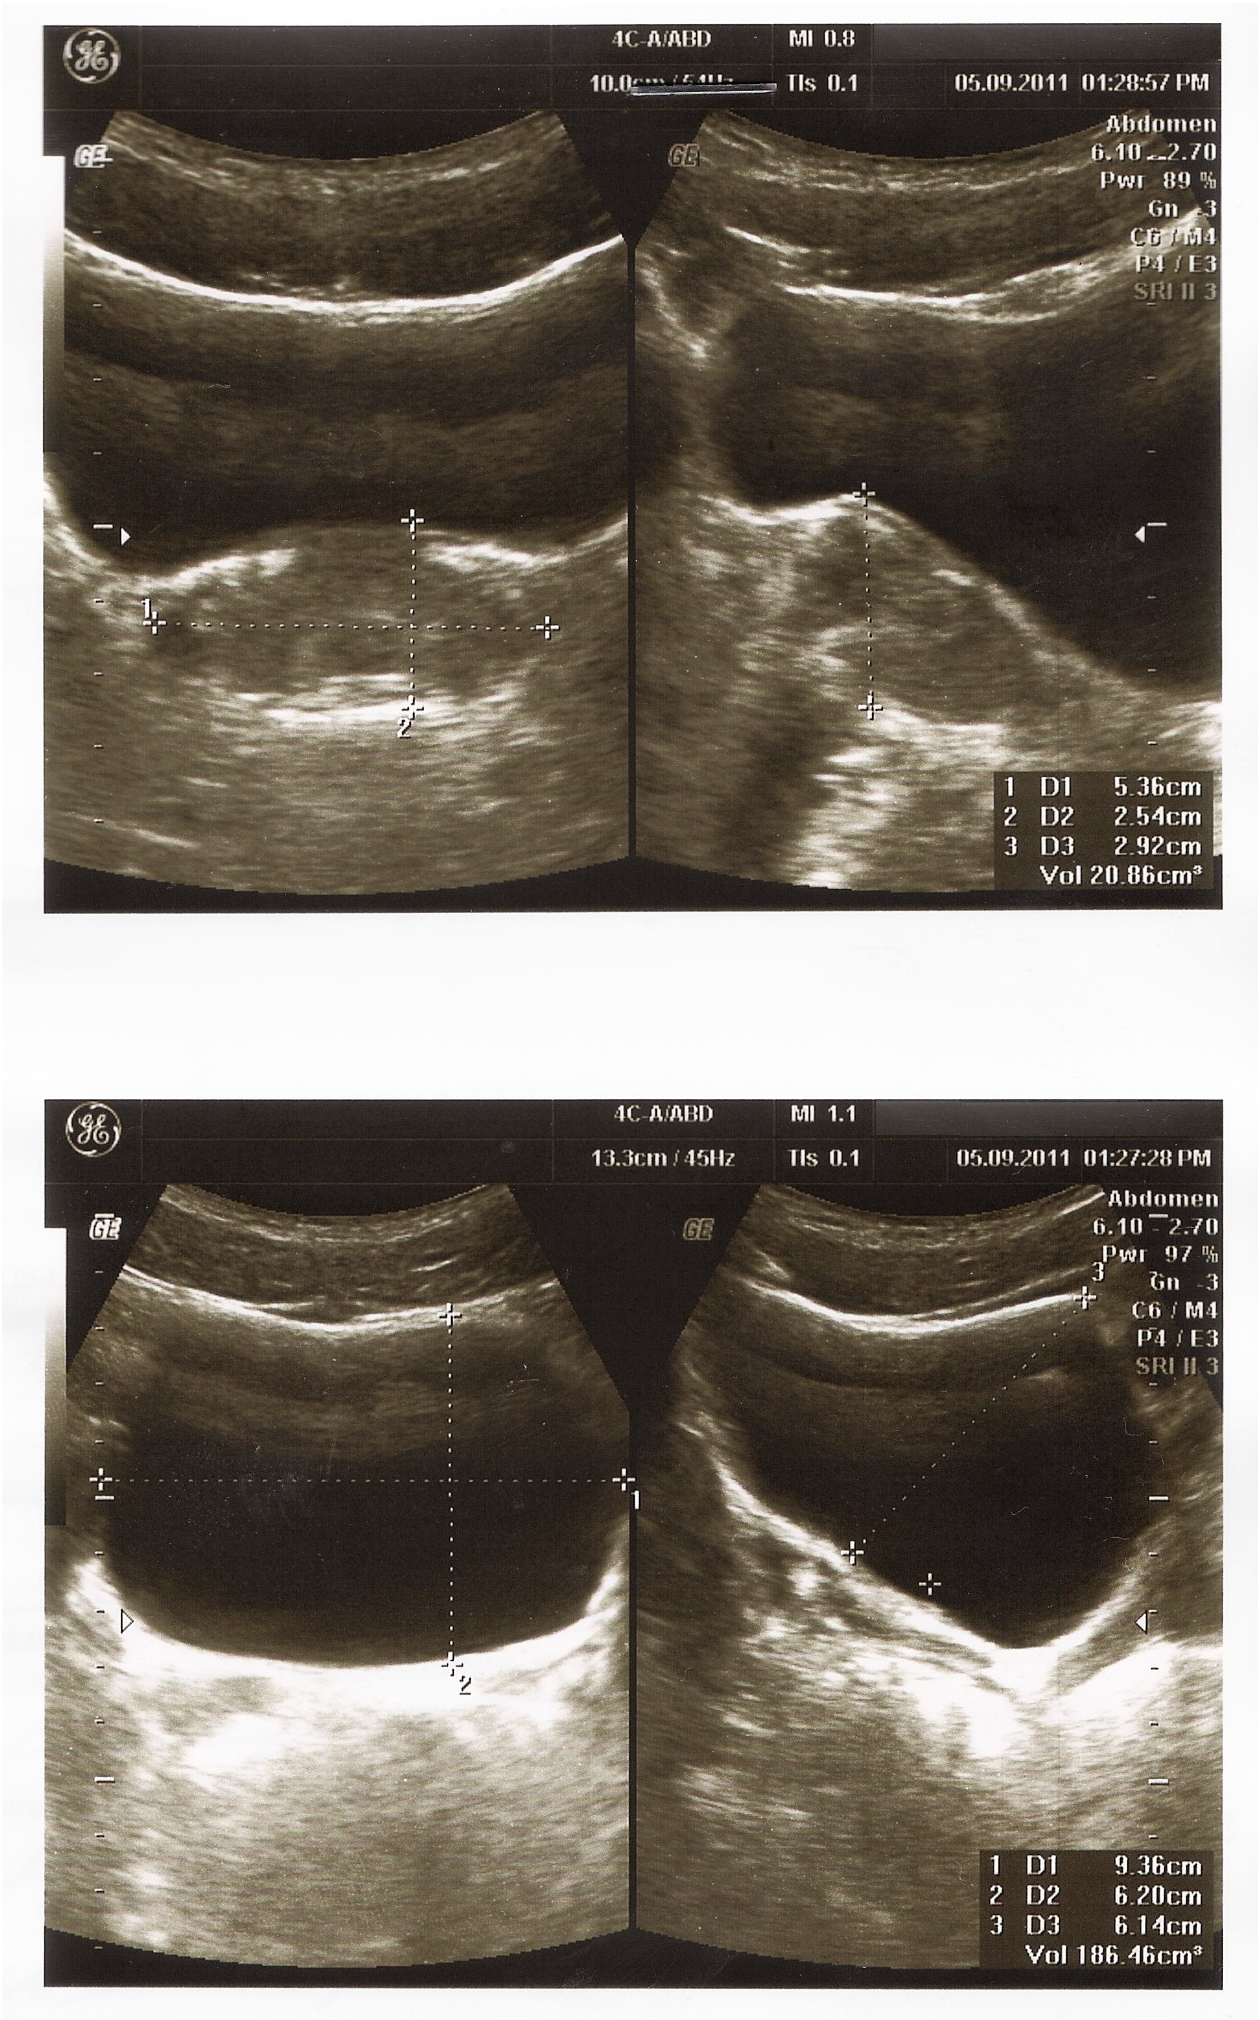

Сходил на прием к урологу, по крови и моче он сказал все в норме, а по узи — простатит. Назначил не дешевое лечение.

Анализы и узи в прикрепленных файлах.